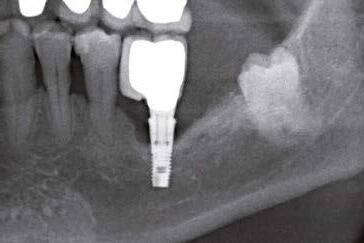

Figura 2. Radiografía tridimensional basal donde se aprecia la ausencia de tabla vestibular en el diente en posición de 41.